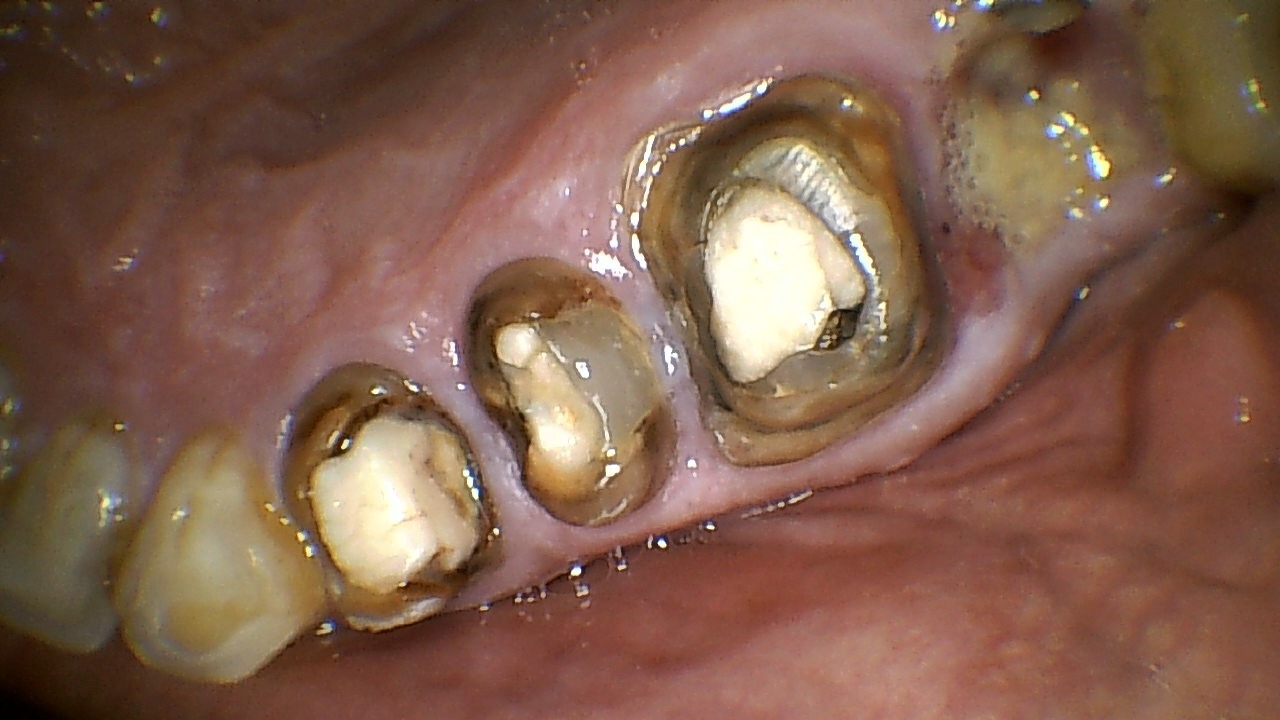

The patient presented with a grossly decayed tooth and significant loss of clinical crown structure. Only a minimal portion of the tooth remained above the gum line, making it difficult to support a conventional restoration.

Before Treatment

- Severely damaged and weakened tooth

- Inadequate structure for conventional restoration

- Difficulty in chewing